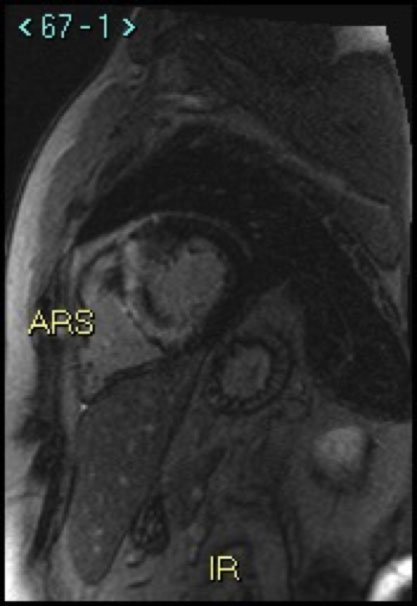

La sindrome di Noonan